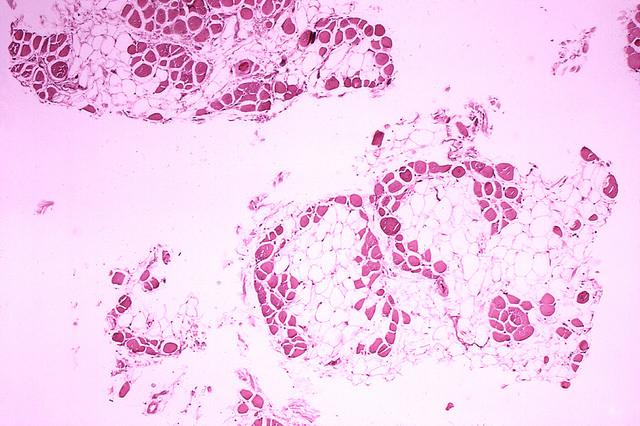

科學家認為,由于肌肉在DMD中不斷受損,衛星細胞的修復負擔如此之大,以至于它們變得精疲力盡,失去了自我復制的能力。衛星細胞對肌肉修復至關重要,因此隨著這些細胞數量的減少,肌肉的自我修復能力會越來越差。相反,受損的肌肉纖維會被脂肪細胞和疤痕組織所取代,從而削弱肌肉,直到它無法再有效地工作。

Emma Kemp 使用Servier Medical Art制作的肌肉結構主圖和說明 iPS 細胞在肌營養不良癥細胞療法研究中的應用?。Edwin P. Ewing, Jr 博士拍攝的杜氏肌營養不良癥患者的肌肉圖像,由美國衛生與公眾服務部公共衛生圖像庫提供?。Mike Kayser的肌纖維照片?,Wellcome Images。?